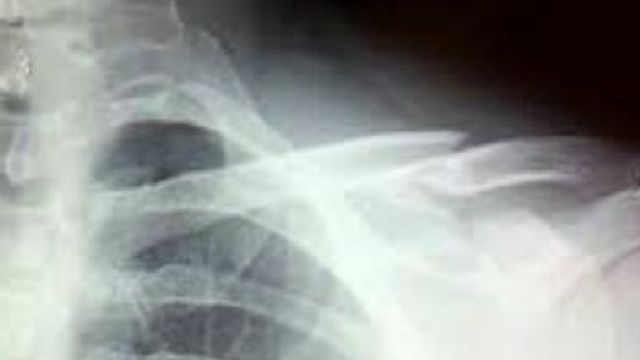

L'infortunio diventa social: subito su Facebook la foto della radiografia

Il ristoratore Joe Bastianich, noto anche per essere uno dei giudici dell'edizione italiana e di quella americana di Masterchef, si è fratturato la clavicola e due costole cadendo in montagna sul monte Zoncolan, in Friuli Venezia Giulia. A dare la notizia è stato lo stesso Bastianich, che su Facebook ha pubblicato la radiografia della clavicola. "Epic crash", ha scritto, ringraziando poi i medici dell'ospedale di Udine che lo hanno curato.